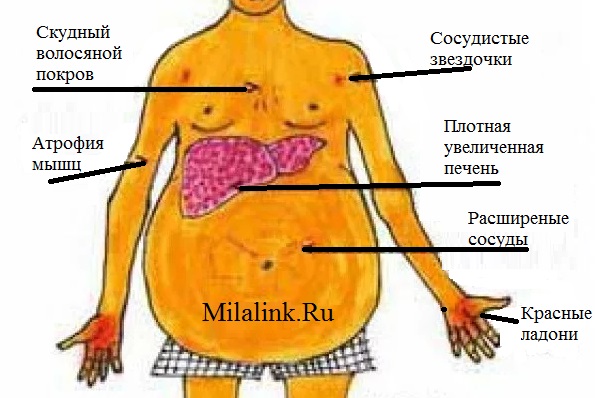

Признаки заболеваний печени: Важные симптомы и рекомендации